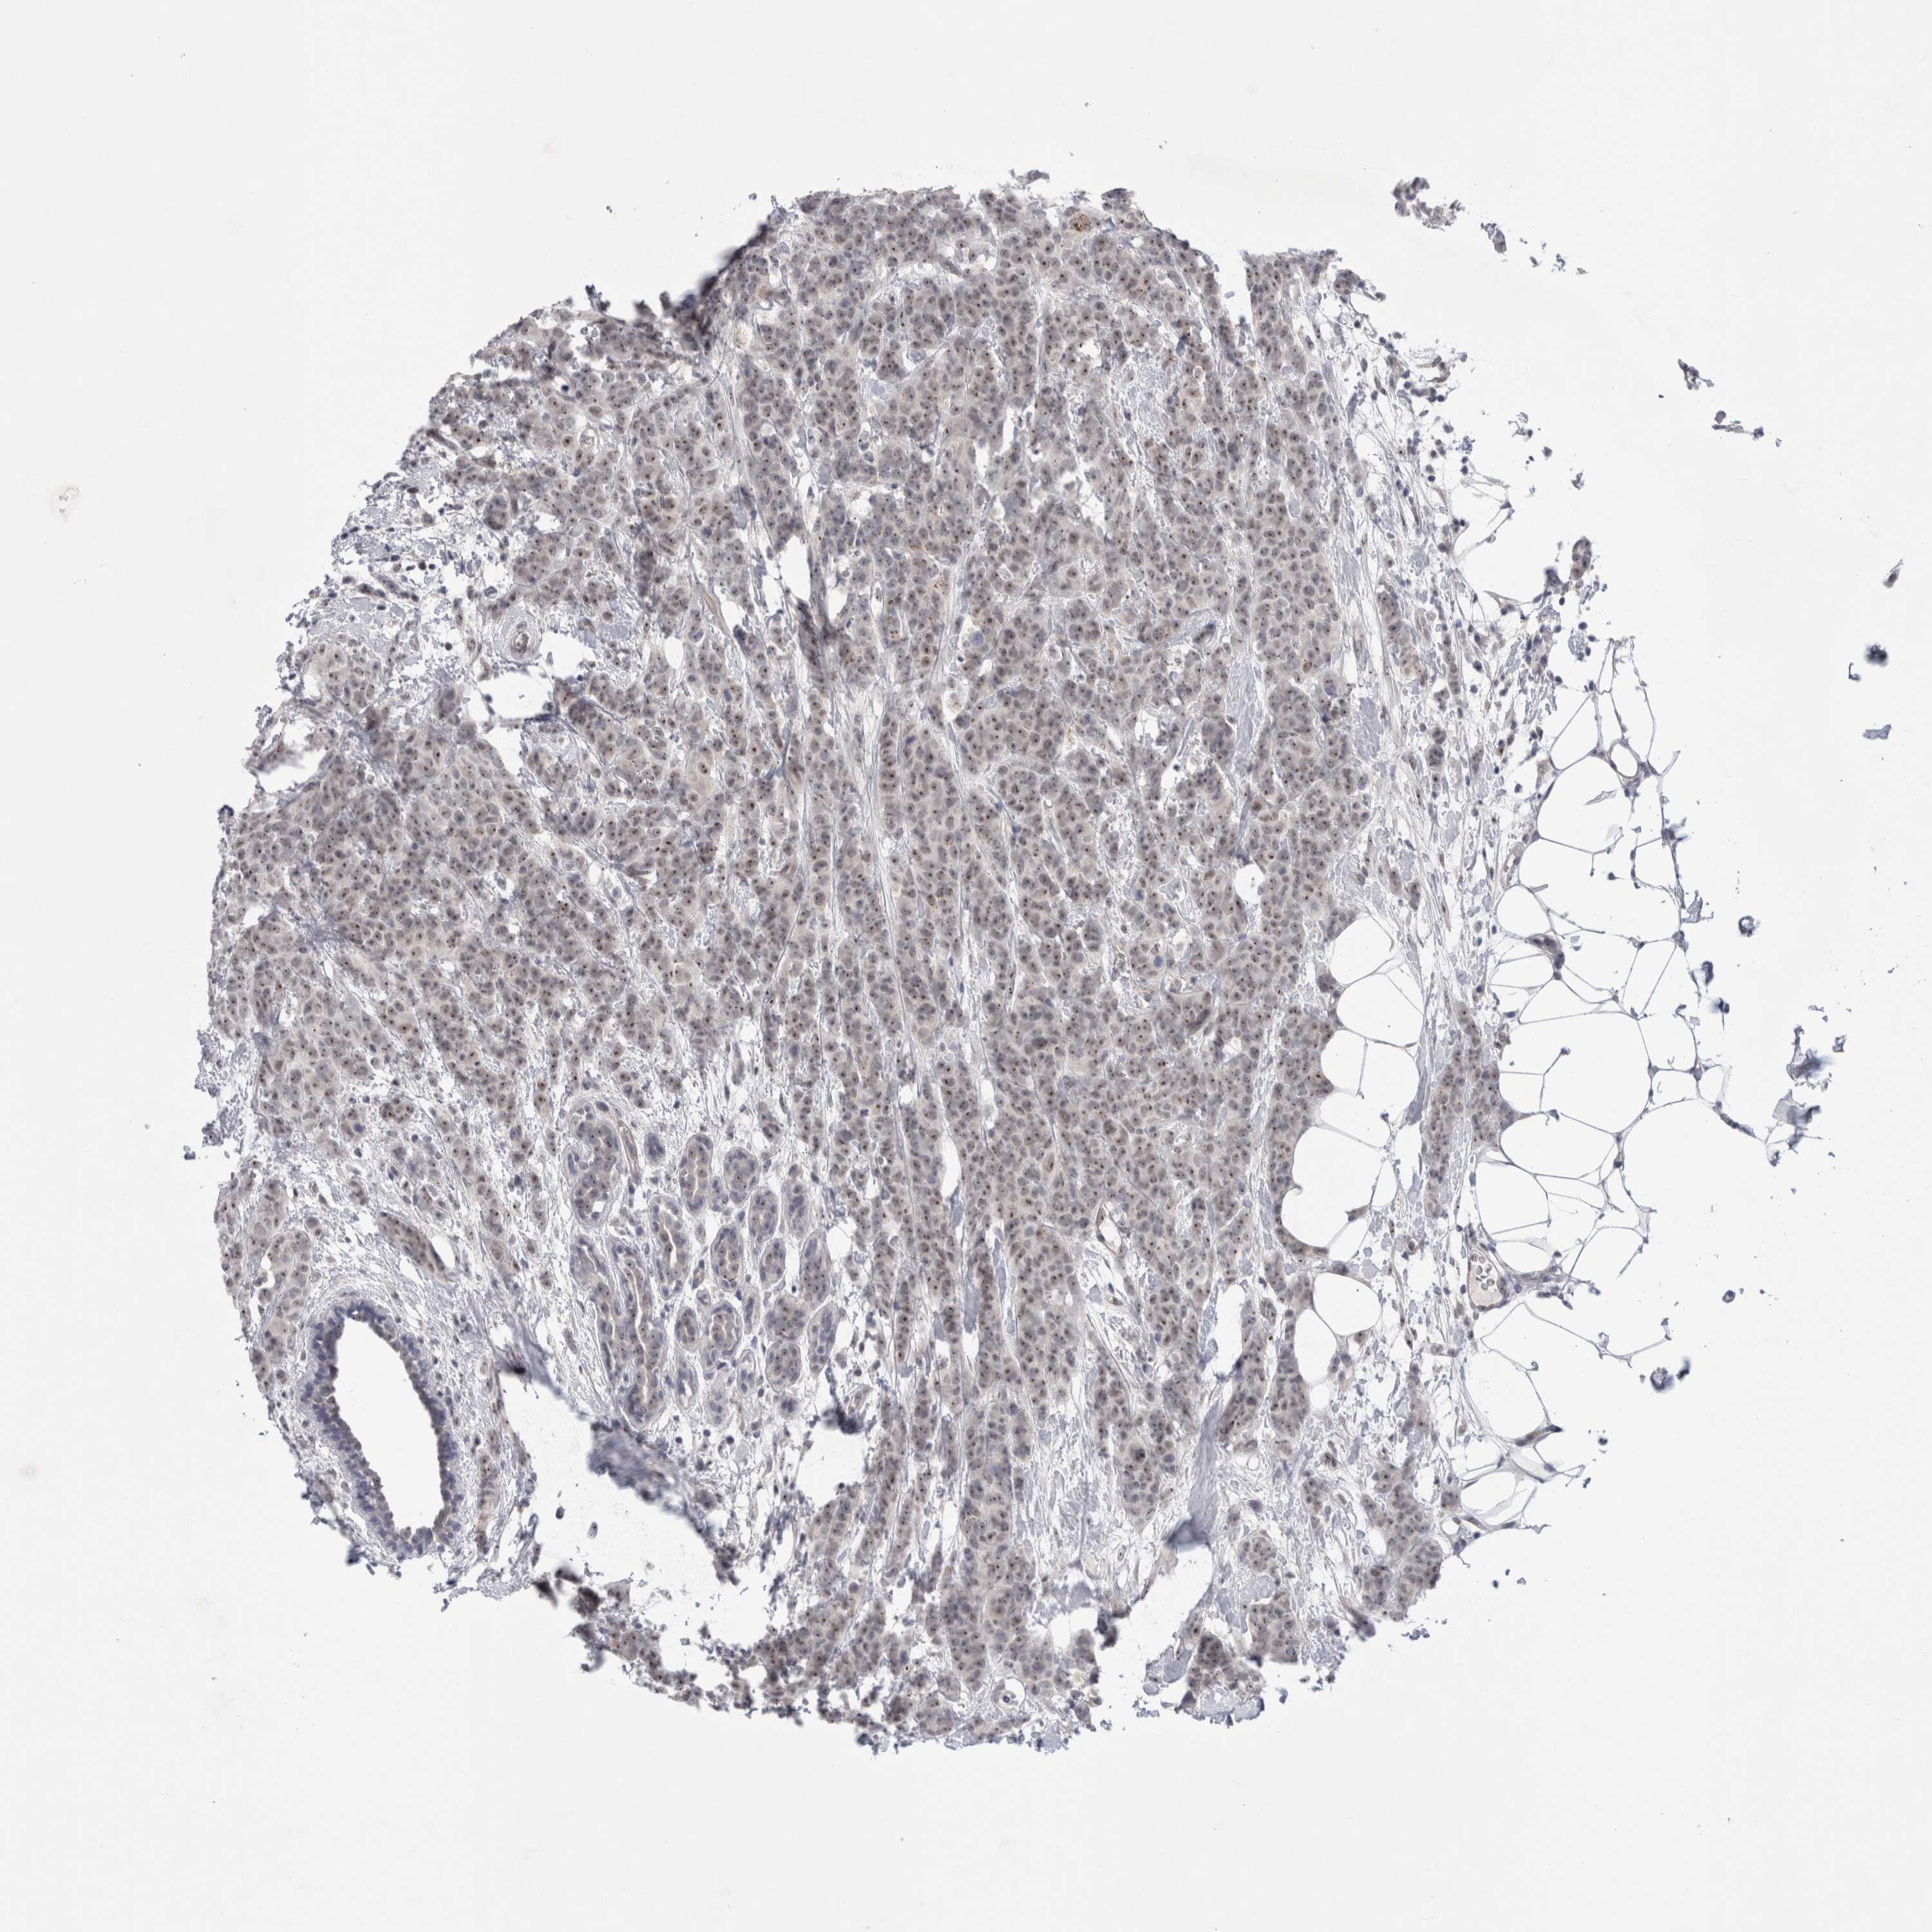

CANCER BREAST CANCER Show tissue menu

BRCA TCGA BRCA VALIDATION PROTEIN EXPRESSION